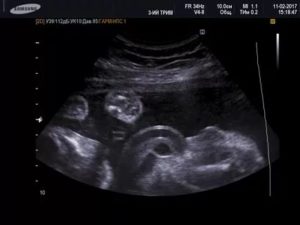

Кисты пуповины встречаются примерно в 3% беременностей. Существуют истинные и ложные кисты. Истинные кисты выстланы клетками и обычно содержат остатки ранних эмбриональных структур. Ложные кисты являются заполненными жидкостью мешочками, которые могут быть связаны с отеком желе Уортона.

Исследования показывают, что оба типа кист пуповины иногда связаны с врожденными дефектами, в том числе и с аномалиями почек и дефектами органов брюшной полости.

Если кисты, также как и любые другие аномалии пуповины, будут выявлены во время обычного УЗИ, врач может порекомендовать женщине пройти дополнительные исследования, такие как амниоцентез и подробное УЗИ, чтобы исключить у ребенка врожденные дефекты.